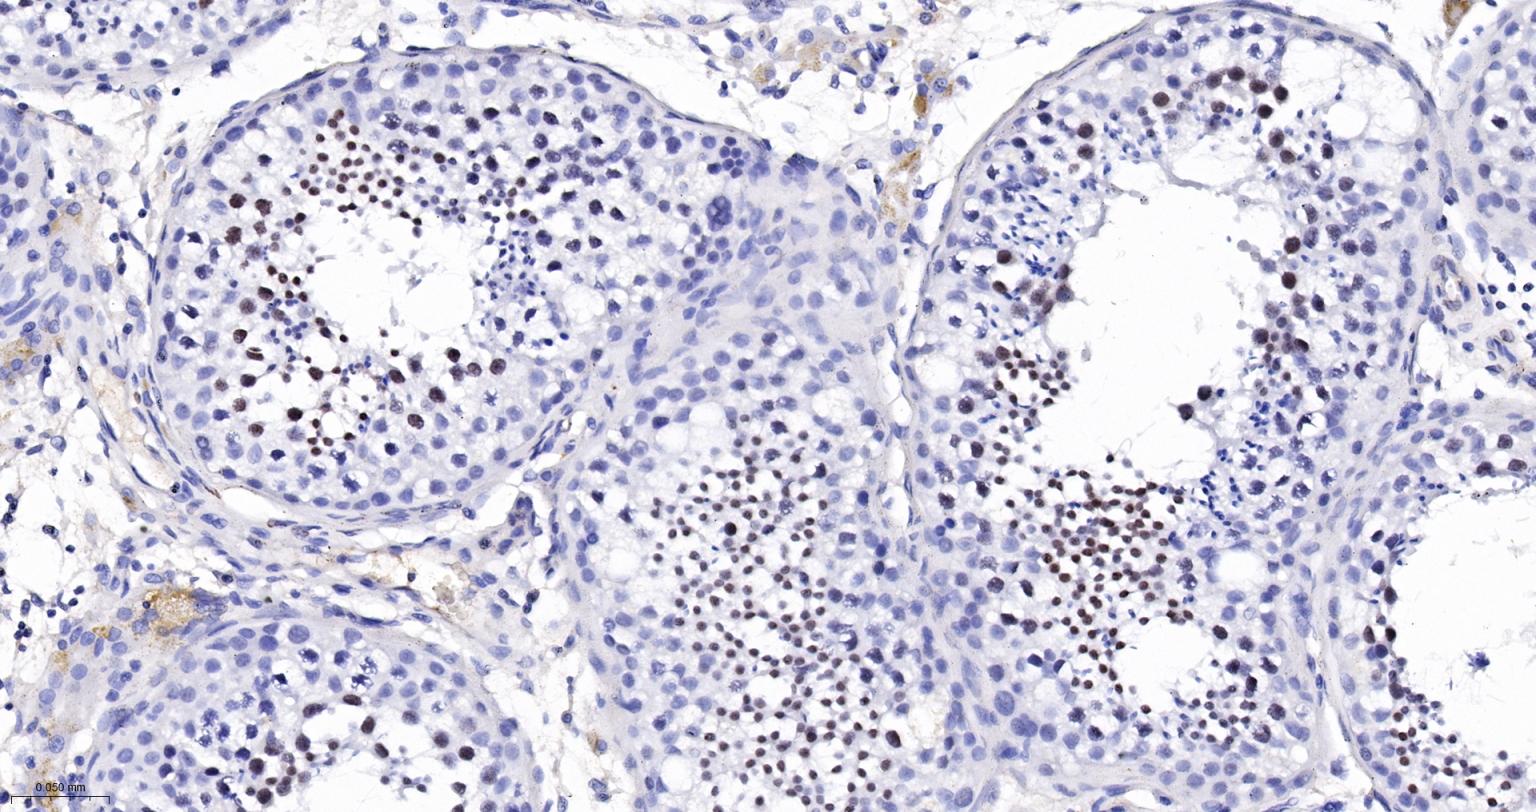

Paraformaldehyde-fixed, paraffin embedded Human Testicles; Antigen retrieval by boiling in sodium citrate buffer (pH6.0) for 15 min; The section was incubated with RAP80 Monoclonal Antibody, Unconjugated (bsm-61657R) at 1:200 overnight at 4°C, followed by conjugation to the bs-0295G-HRP and DAB (C-0010) staining.